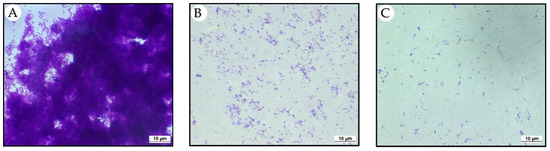

2.2. EBEO Inhibits the Formation of Streptococcus mutans Biofilm

4.4. Anti-Biofilm Assay on Circular Coverslip

- Control Group: S. mutans + BHI + 1% Glucose (CON);

- Group 2: S mutans + BHI + 1% Glucose + EBEO in MIC (EBEO 62.5);

- Group 3: S. mutans + BHI + 1% Glucose + EBEO 10×MIC (EBEO/625).